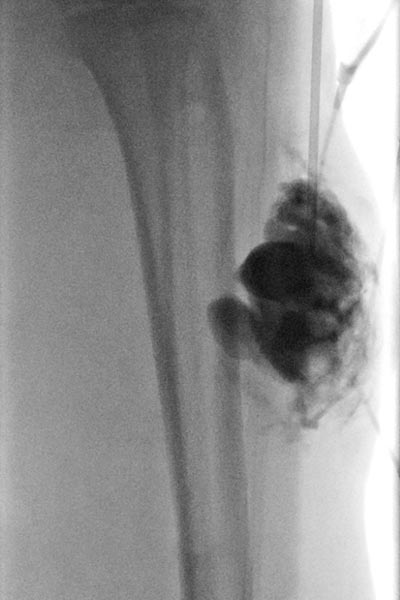

Es erfolgte wegen des deutlichen Progresses und den sich immer wieder entzündenden, schmerzhaften Anteilen eine Sklerosierungstherapie mit Doxycyclin (Konzentration 10 mg/ml) der zystischen Anteile. Das Durchleuchtungsbild zeigt die Punktion und Kontrastierung der Zysten vor Injektion des Sklerosierungsmittels.

Da das klinische Ergebnis noch nicht zufriedenstellend war, erfolgte eine erneute Sklerosierungsbehandlung (hier das zugehörige Durchleuchtungsbild nach Kontrastmittelinjektion in die Läsion). Eine notwendige Wiederholung war anhand der Größe der Läsion auch von vornherein zu erwarten. Diesmal gleichzeitig mit einer lokalen sonographisch gesteuerten Biopsieentnahme zur histopathologischen Subdifferenzierung der Slow-flow-Gefäßmalformation.